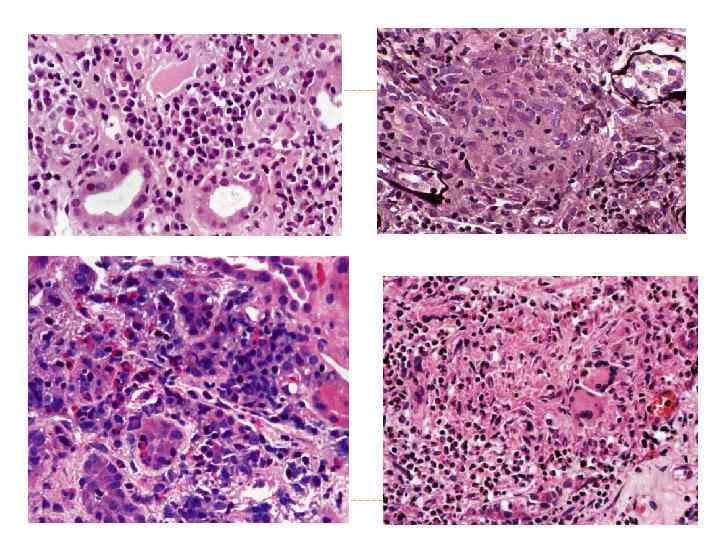

Некроз эпителия извитых канальцев почки Острая почечная недостаточность

острый пиелоне фрит Гнойное воспаление с абцедированием Хронический пиелонефрит Лимфогистиоцитарная инфильтрация и склероз стромы, Перигломерулярный склероз Кистозная атрофия канальцев «тиреодизация почки» Ассиметричное сморщивание почек с грубыми рубцами